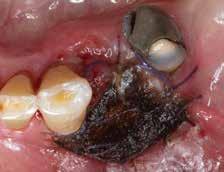

Wie in DentUnique (Ausgabe 01-2021) ausführlich berichtet, wurde ein 72-jähriger Patient mit einer schriftlichen Überweisung vom niedergelassenen Zahnarzt mit Verdacht auf Epulis in der Region von 34 im März 2020 auf der Notfallambulanz der Universitätszahnklinik in Wien vorstellig. Der Patient gab zusätzlich an, dass er seit Jänner bereits mehrere zahnärztliche Ambulatorien besucht habe. Im Jänner wurde aufgrund starker Schmerzen bei einem niedergelassenen Zahnarzt eine Wurzelkanalbehandlung an Zahn 34 begonnen und der Patient antibiotisch abgeschirmt (1 g Augmentin wurde zehn Tage eingenommen), jedoch brachten Wurzelkanalbehandlung und Antibiotika-Gabe keine Besserung hinsichtlich der Schwellung zwischen Zahn 33 und 34.

Zum Zeitpunkt der Erstaufnahme (Abb. 1a, März 2020) in der Notfallambulanz der Universitätszahnklinik Wien gab der Patient keine Schmerzen an, jedoch eine seit mehreren Wochen zunehmende Schwellung, bukkal- und lingualseitig zwischen Zahn 33 und 34. Beim Patienten wurde eine detaillierte klinische Untersuchung durchgeführt und eine sehr starke Klopfdolenz des Zahnes 34 sowie Sondierungstiefen von über 12 mm, Blutung auf Sondierung und Mobilitätsgrad II diagnostiziert. Im Kleinröntgenbild wurde ein Knochenverlust beobachtet (Abb. 1b). Der Patient wurde über die Nichterhaltungswürdigkeit des Zahnes 34 aufgeklärt und der Zahn wurde in derselben Sitzung restlos entfernt. Das Granulationsgewebe Abb. 2

dass die Schwellung in der Region 34 nach wie vor vorhanden sei und die Schmerzen seit der Zahnentfernung noch stärker geworden seien. Am 16.4.2020, nur drei Wochen nach der Erstaufnahme, wurde der Patient durch Dr. Domic (Abteilung für Orale Chirurgie) begutachtet. Der Patient gab an, trotz Zahnextraktion und Nachbehandlung zunehmende Schmerzen und eine granulomatöse und hyperplastische Schwellung in der Region von 34 zu haben. Die granulomatöse Schwellung in der Region von 34 wurde fotodokumentiert (Abb. 2 u. 3) und der Patient wurde über die Notwendigkeit einer sofortigen Biopsie aufgeklärt.

Abb. 3

Nach Gabe einer Lokalanästhesie wurden mit einem Kauter eine partielle Exzision der granulomatösen Schleimhautveränderung und im Anschluss eine Biopsie durchgeführt. Die Wunde wurde mit einem Hämostyptikum (Tabotamp®) versorgt (Abb. 4 u. 5) und der Patient wurde in einer Woche zur Kontrolle, inklusive Nahtentfernung und histologischer Befundbesprechung, einbestellt.